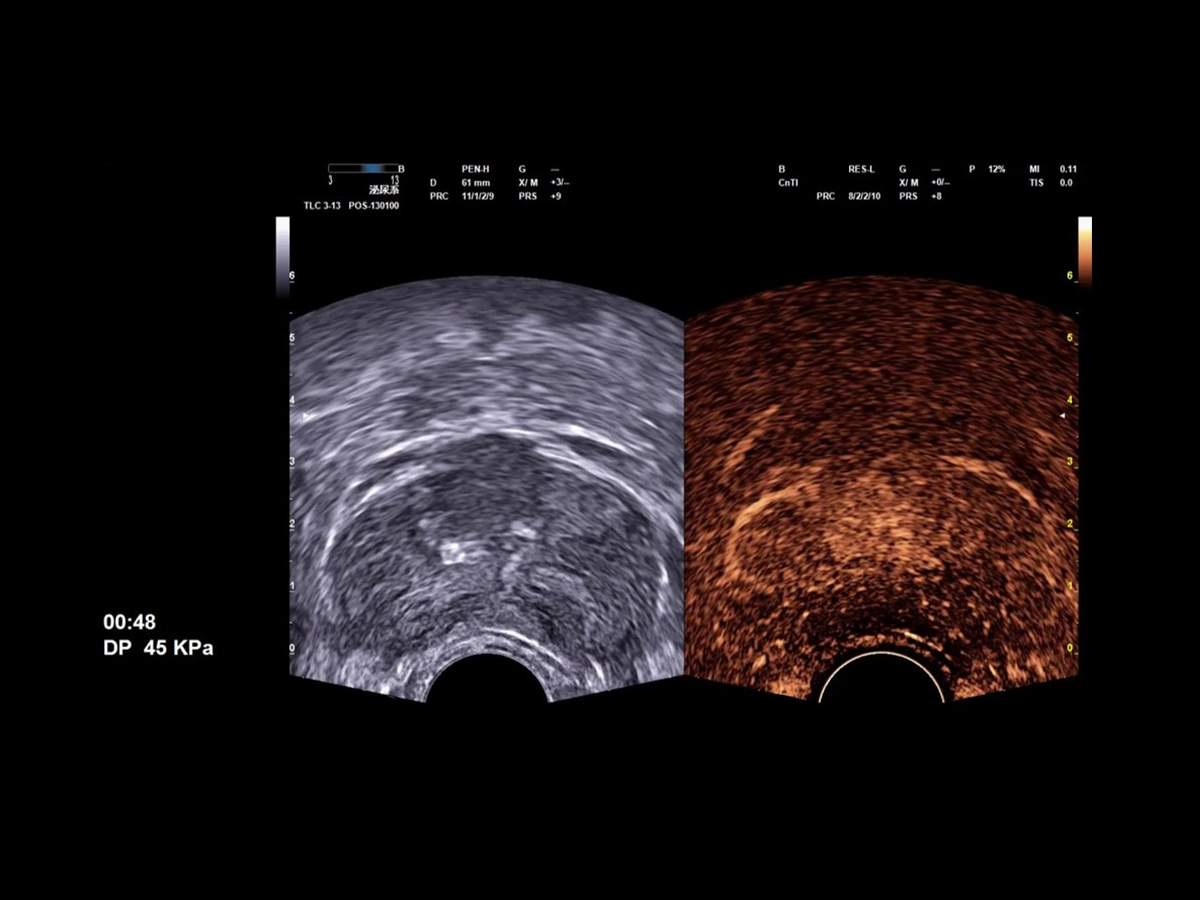

ElaXto and QElaXto 2D are Esaote’s strain and shear wave elastography technologies, which provide information on tissue elasticity by displaying a color-coded map representing prostate stiffness either relatively or quantitatively.

QElaXto 2D on sagittal view in suspected anterior region

CnTI™ is Esaote’s CEUS technology that helps to identify suspicious areas in the prostate, helping to target areas to be biopsied. Furthermore, it can be used for focal therapy follow-up.

The CnTI™ guarantees a very high sensitivity in detecting contrast media agents, while maintaining long persistence of the contrast bubbles.

CnTi™ (Prostate perfusion study - Suspected anterior lesion)